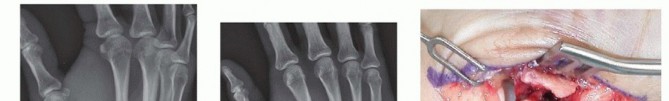

Fixation Strategies for Rolando and Comminuted Patterns

Rolando fractures present a significantly higher degree of complexity. The classical Y or T pattern often precludes simple lag screw fixation. In these instances, mini-fragment plating is the gold standard. T-plates or specialized condylar plates are contoured to fit the complex geometry of the metacarpal base. The articular fragments are first reduced and provisionally pinned, essentially converting the complex intra-articular fracture into a simpler two-part extra-articular fracture. The plate is then applied to buttress the articular fragments and bridge the metaphyseal comminution to the diaphysis.

Image